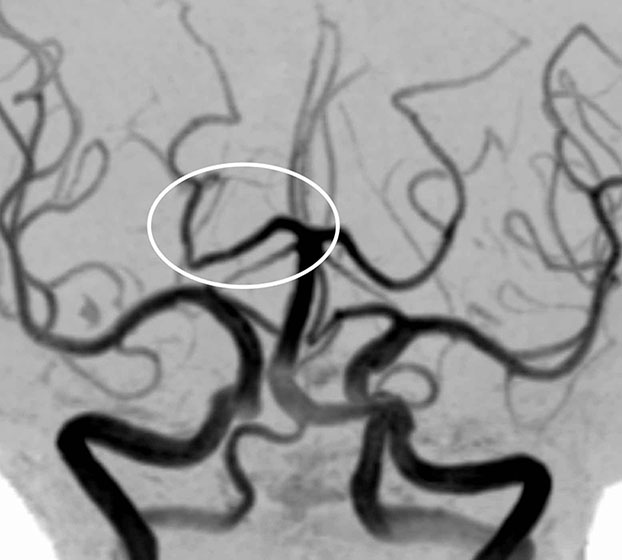

MRA検査(脳動脈の撮像)で見ても、

脳梗塞の原因となるような動脈硬化はなく、いたって正常な状態でした。

やはり症状からは一過性全健忘と診断されますが、実際には海馬の脳梗塞が原因という事になります。